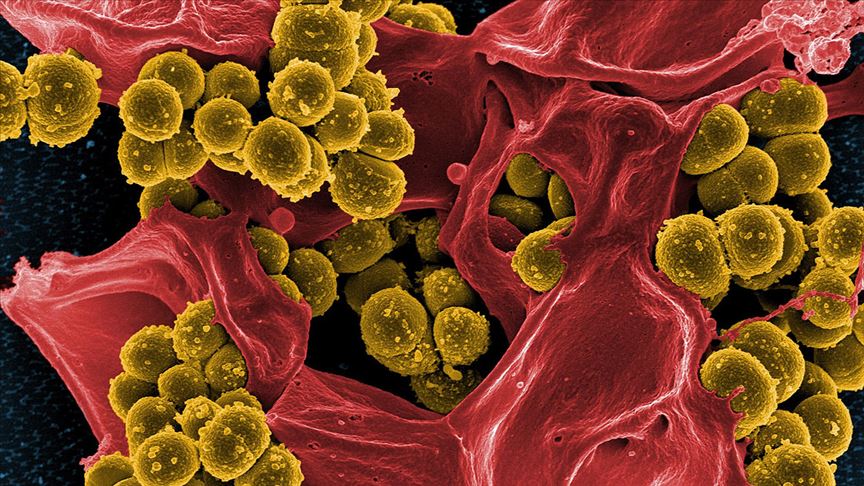

Genelde insan yapımı su sistemlerinde bulunan lejyonella bakterisi, en fazla, verimliliği düşürmemek adına daha az dezenfeksiyon işleminin yapıldığı yapılar ile otel, yurt ve hastane gibi çok sayıda kişi tarafından kullanılan binalarda görülüyor.

Etken bakteri olan Legionella genellikle göller, nehirler ve akarsular dahil tatlı su ortamlarında bulunur. Legionella ayrıca toprakta da yaşayabilir, fakat çoğu insan topraktan bakteri kapmaz. Lejyoner hastalığını ev tesisat sistemleri yoluyla kapmak mümkün olsa da, çoğu salgın otel gibi toplu yaşama dahil büyük binalarda meydana gelir. Çünkü karmaşık dağıtım sistemleri bakterilerin daha kolay çoğalıp yayılmasına izin verir.

Ilık suda kolaylıkla çoğalabilen bakteri, genellikle bir binanın kirlenmiş su dağıtım sistemi yoluyla yayılır. Fakat hastalık havada asılı duran su damlacıklarının solunması yoluyla insanlara bulaşır. Bakteri o kadar küçüktür ki, su buharı gibi küçük su damlacıklarının içine yerleşerek havaya karışabilir. Kontamine suların bulunduğu sauna, hamam veya kaplıca havuzu gibi sıcak sulardan çıkan buhar damlacıklarının solunması ile bakteri akciğerlere ulaşır. Nadiren bakteri ile kontamine suların içilmesi sırasında soluk borusuna kaçmasıyla da bulaşabilir. Kişiden kişiye yayılım söz konusu değildir. Uygun şekilde bakımı yapılmadığında lejyonella için temel üreme alanları şunları içerir: